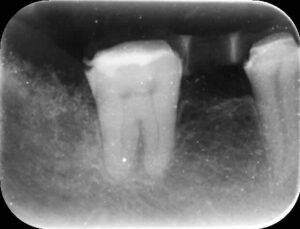

ーアップライト後ー

上のレントゲン写真のように奥歯が手前に傾いてしまっている歯を正しい位置に戻してあげる治療です。